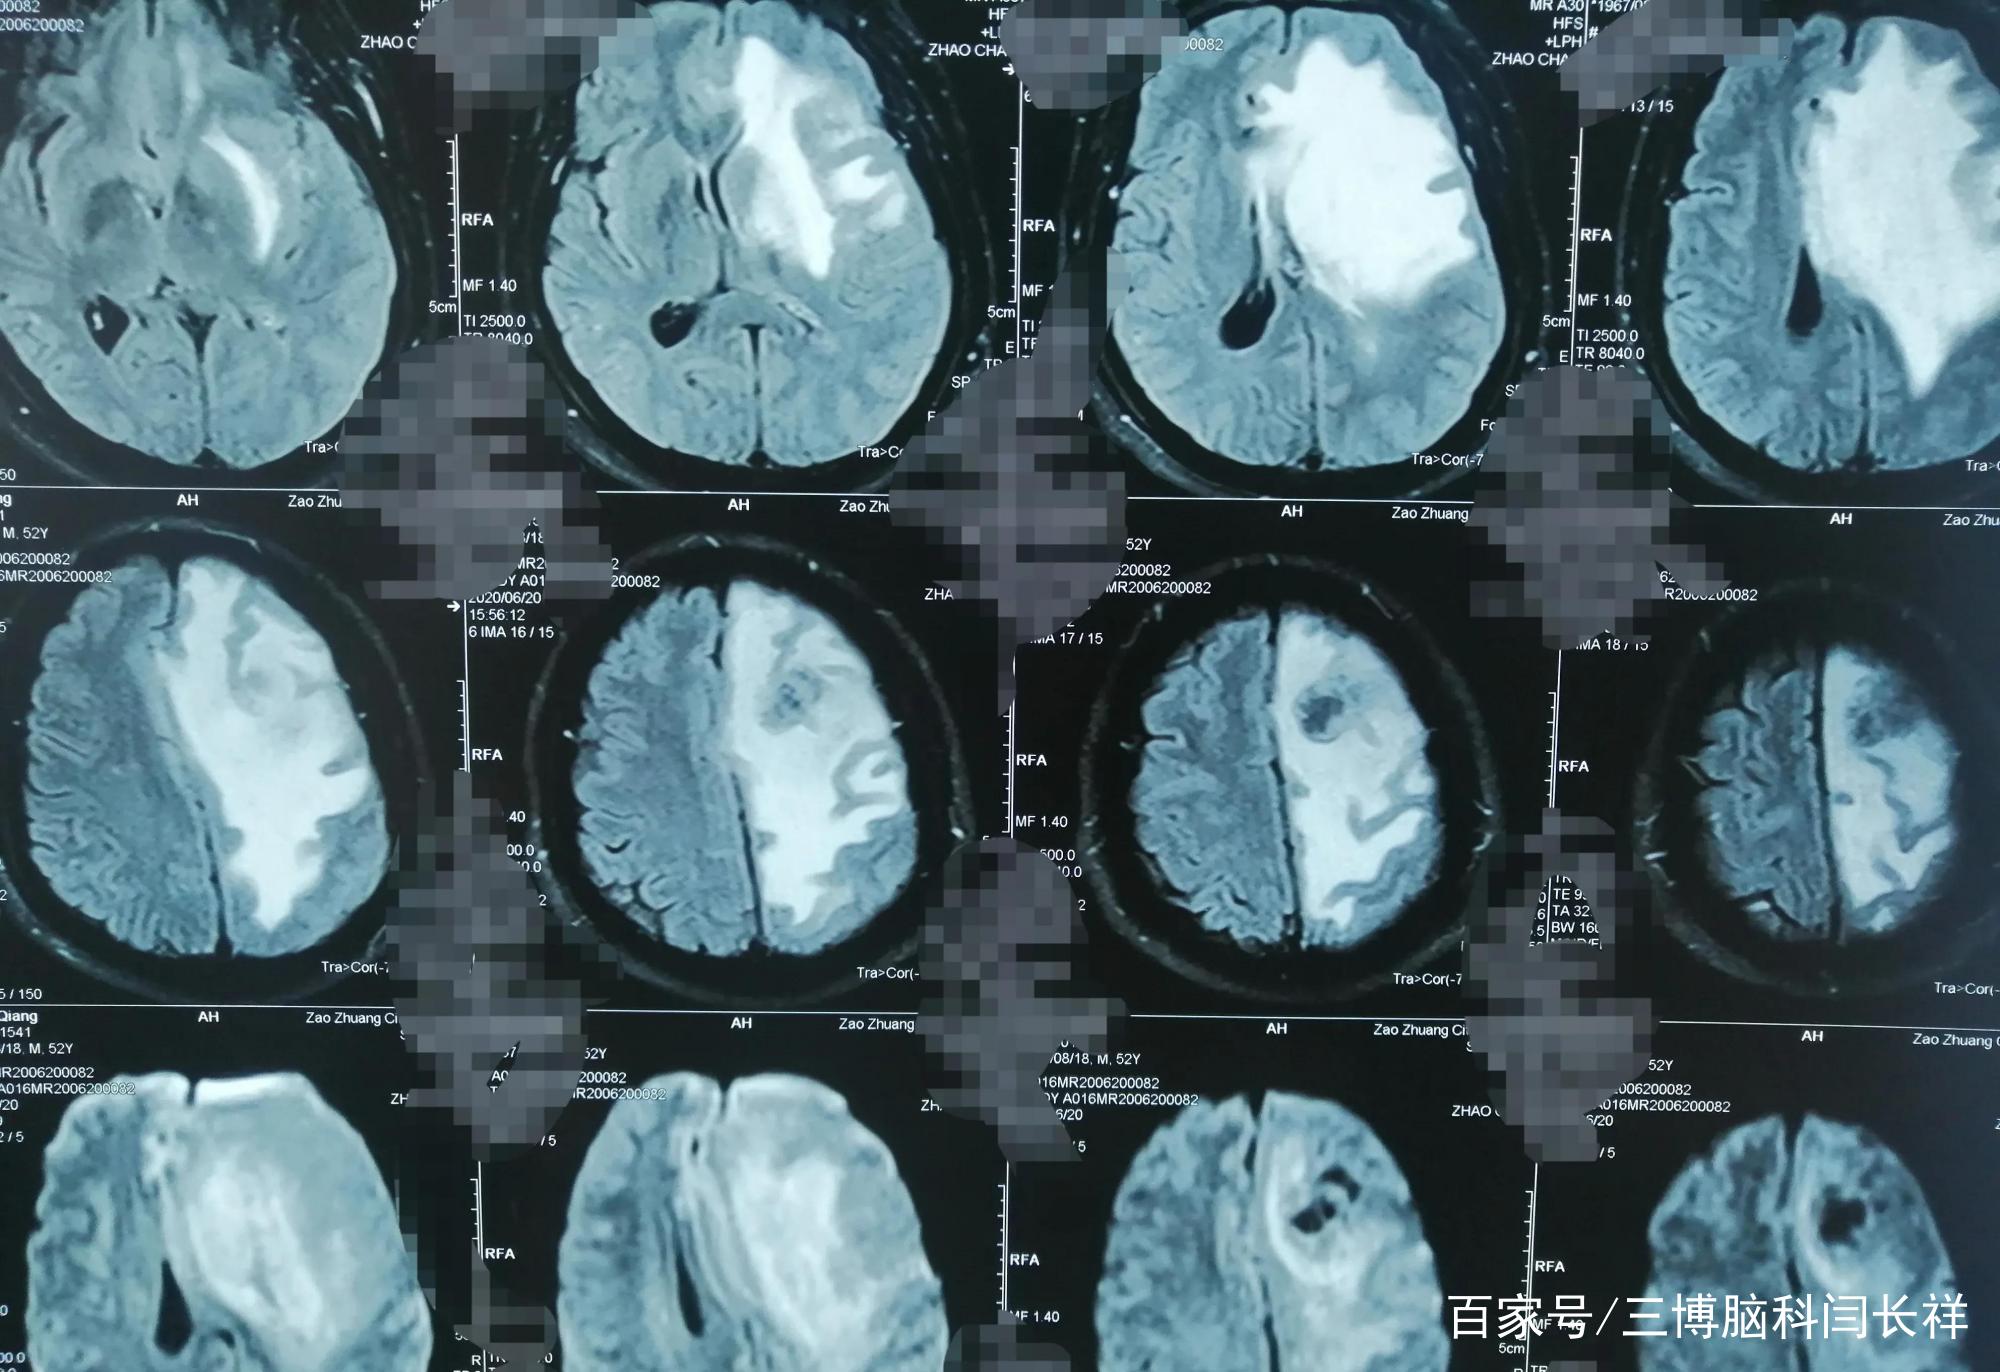

初步诊断:左额胶质瘤。

左侧大脑掌管右侧肢体活动,就是因为左额这里长了肿瘤,所以才导致老孙右脚踩刹车像是演慢动作,这是因为腿脚不灵便了呀,反应力变差。说话变慢也是同样的道理。

6月29号,老孙于全麻下行左额开颅肿瘤切除术。手术顺利。